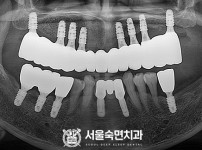

상악동거상술, 뼈이식 / 숙면임플란트 12개 - 오스템임플란트 (김*현님)

해당 게시물은 의료법 제56조에 의거하여 로그인 후 열람이 가능합니다.

구분 임플란트